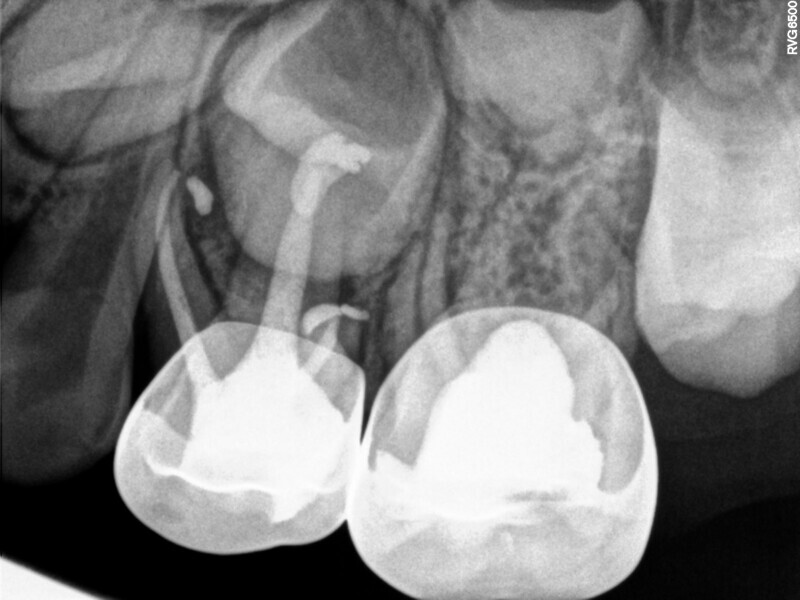

Cas 1 (Figs 1-4)

Cette patiente âgée de 4 ans et 7 mois présentait une douleur qui affectait la seconde molaire temporaire inférieure droite depuis plusieurs jours. L’examen clinique a révélé un gonflement du versant vestibulaire de la gencive et un œdème facial, ainsi qu’une carie occlusale profonde.Un diagnostic de nécrose pulpaire et d’abcès apical symptomatique ayant été posé, un traitement a été prescrit à la patiente, afin de maîtriser l’infection aiguë, et un nouveau rendez-vous a été fixé après l’antibiothérapie. Lors du deuxième rendez-vous, elle ne présentait plus aucune douleur et l’abcès buccal s’était partiellement résorbé. Il a été décidé de procéder à une pulpectomie et à la restauration de la dent. Dans ce cas, la dent présentait une extrusion excessive de matériau d’obturation. Après 15 mois, la réévaluation a confirmé l’absence de signes cliniques ou radiologiques pathologiques, et une apposition osseuse était visible dans la zone de la furcation.